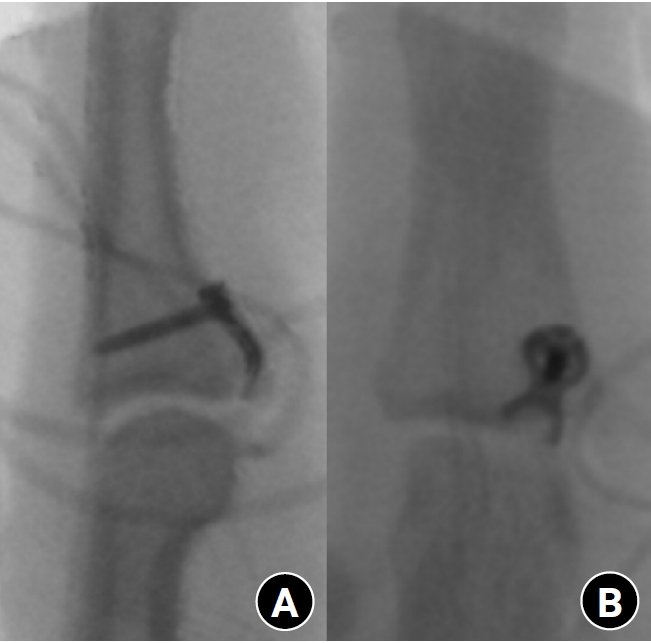

Fig. 4.

Radiographs during follow-up. (A) Bone union after treatment with the hook plate. (B) Appearance after implant removal.

Once both clinical and radiographic union were confirmed, implant removal was recommended. Implant removal was routinely performed after confirming bone union, and the removal timing was considered equivalent to the time of union. Removal was recommended for all patients, but one patient declined secondary surgery. After bone union was achieved, the plate was removed (Fig. 4).

In our study, implant removal was performed in eight out of nine digits. Following implant removal, good joint stability and a slight increase in the ROM of the PIP joint were observed. No additional manipulation such as brisement was performed at the time of implant removal, and the improvement in ROM occurred gradually during postoperative rehabilitation rather than immediately after removal. This improvement in ROM indicates successful fracture healing and postoperative recovery. Although plate removal after bone union still remains controversial, we experienced limitation of joint motion and restoration of total ROM after removal in all patients. Additionally, plate removal can prevent potential tendon adhesion and joint stiffness that may be caused by the plate. We believe that implant removal should be performed promptly after bone union has been confirmed to prevent adhesion and facilitate early recovery of motion. We proposed that the plate should be removed after bone union to gain complete ROM.